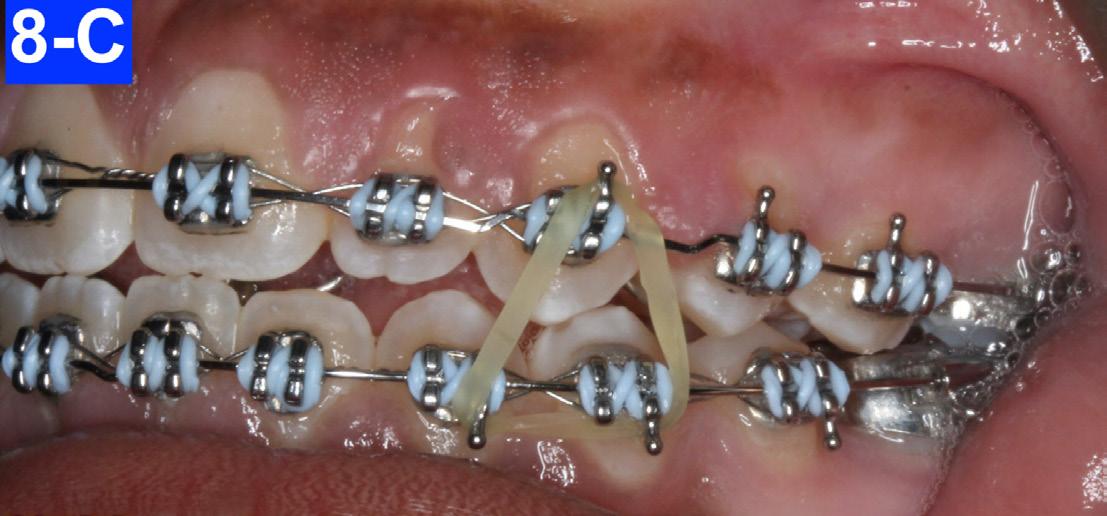

The maxillary and mandibular six anterior teeth were undertied with a lace-back (a .010 ligature tie) to crystalize the space closure. There was an open coil spring between #44(28) and #45(29) to close the space between the first bicuspid and the cuspid. In addition, there were ¼ " , 4.5 oz triangular elastics stretched between the maxillary cuspids and mandibular cuspids and bicuspids (8-A, B, C, D, E).

Fig. 8-A: Triangular elastics, frontal view

Fig. 8-B: Triangular elastics, right lateral view

Fig. 8-C: Triangular elastics, left lateral view

After eight months of treatment, the maxillary habit breaker was removed. We added box elastics (5/16” x 6.5 oz) that were stretched around the mandibular cuspids and maxillary laterals, to accelerate the closing of the anterior open bite. The patient was already very happy with the progress and the amelioration of her posed smile (Figure 9-A, B, C, D).